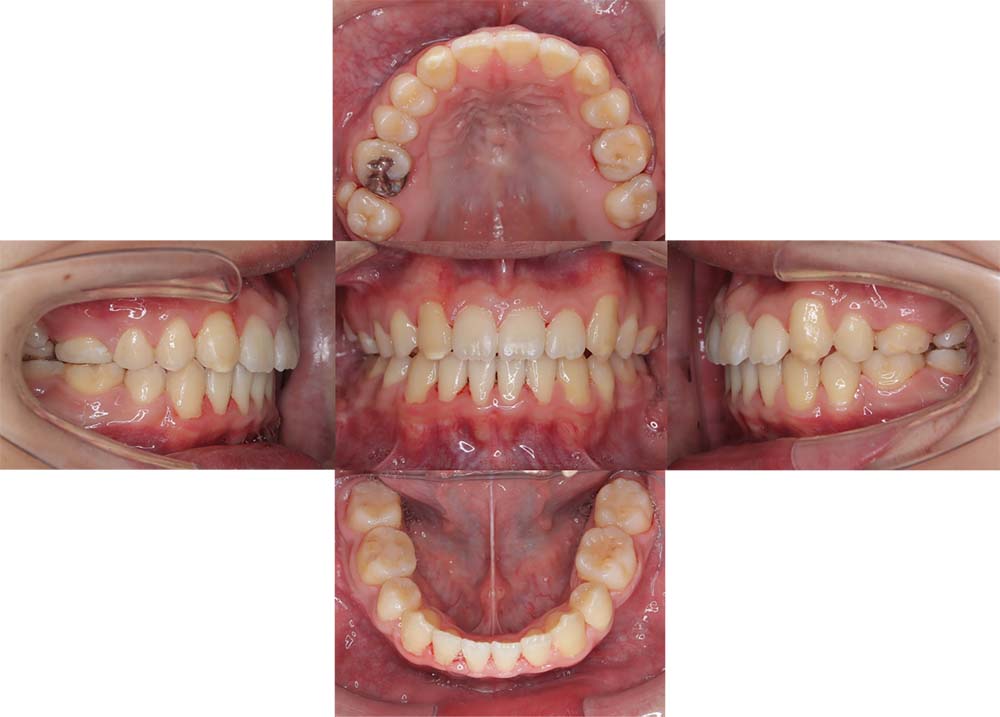

症例03

| 主訴 | 歯並びがガタガタしている。 |

| 診断名あるいは主な症状 | 過蓋咬合、叢生 |

| 年齢/性別 | 26歳・女性 |

| 矯正ステージ | 大人の矯正治療 |

| 治療方法 |

ワイヤー矯正 歯科矯正用アンカースクリュー(3本) |

| 抜歯部位/抜歯有無 | 抜歯 |

| 治療内容 | 上下顎の奥歯を後方に移動後、ガタガタの改善と上下顎前歯を後退させた。 |

| 費用 |

90万円程度(2025.10時点の料金となります。) ※矯正基本料金、アンカースクリュー、審美ブラケットを含む |

| 治療期間 | 2年8ヶ月 |

| 主なリスク・副作用 | 痛み、歯根吸収、歯肉退縮、虫歯、後戻り |